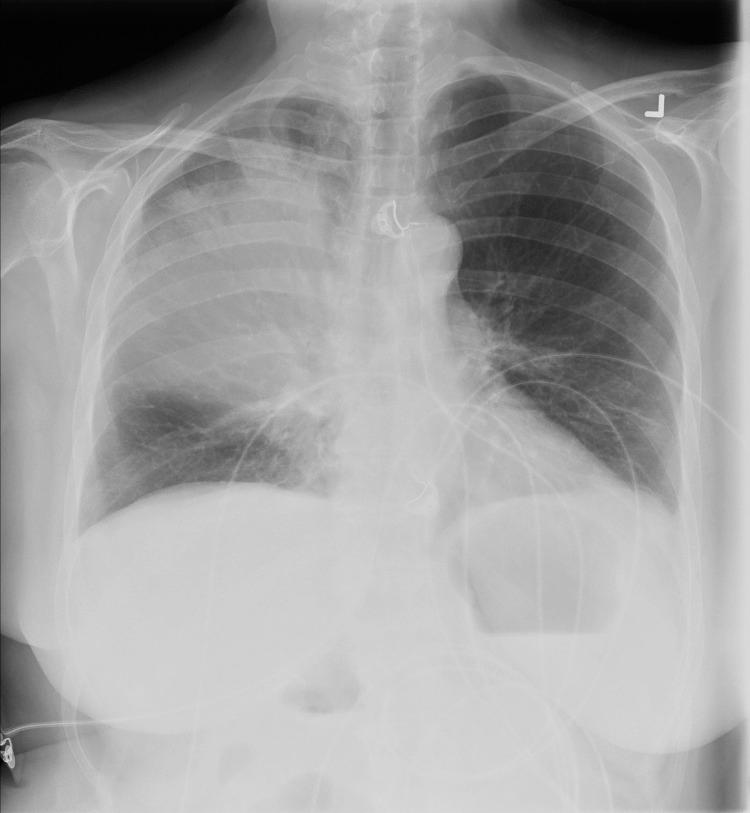

Legionella pneumophila serotype 1 pneumonia in patient receiving adalimumab.

We describe a case of severe pneumonia caused by Legionella pneumophila serotype 1 in a woman receiving the tumor necrosis factor-α antagonist to treat rheumatoid arthritis. As use of tumor necrosis factor-α inhibitors increase, clinicians should consider their possible association with legionellosis.